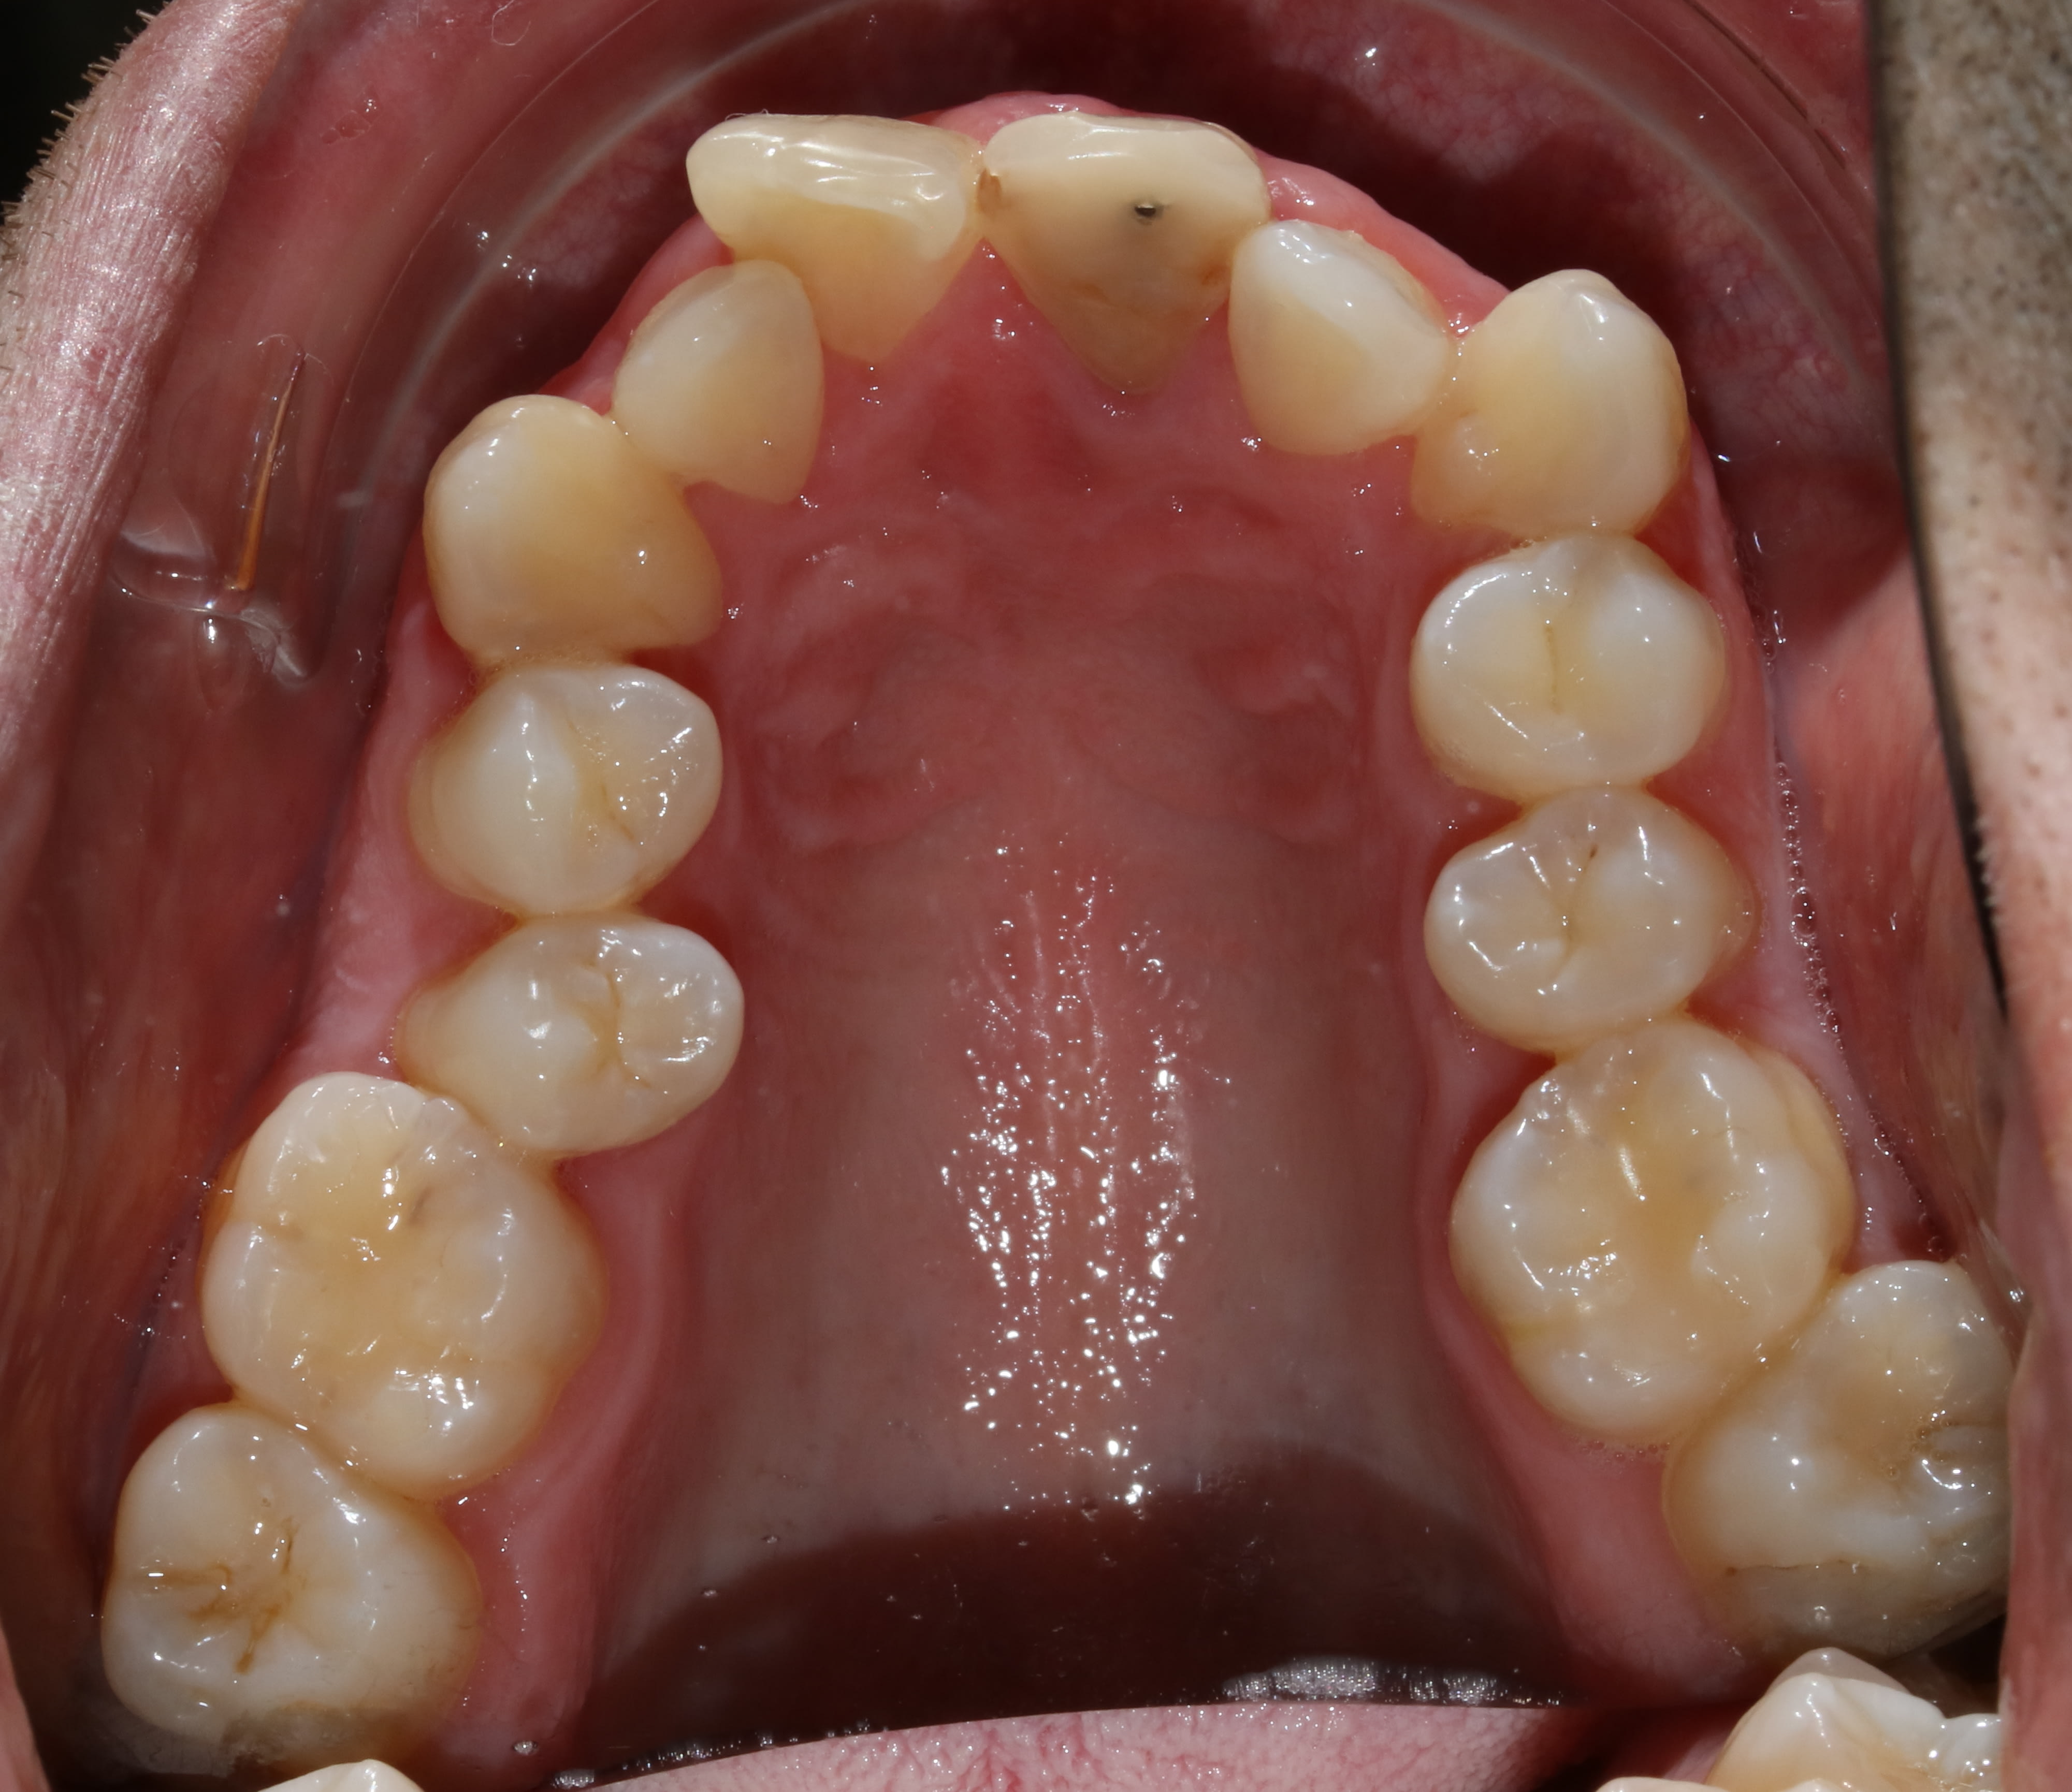

Patient quarante cinq ans. Bruxe, serre, tendu acouphénes, cephallées, visites recurrentes chez les osteo sans resultats, cadre sup ingenieur boite helicos bien connue, stressé++++, vit à 200 à l'heure....

Ici pas possibilté remonter la dv car en quasi bout à bout de base.

Dents naturelles m'interdisant d'envisager de la prothèse en premiere intention.

Faire une gouttiere l'aurait peut être amené à un positionnement plus confortable mais aurait conduit à reconstruire ensuite les dents pour se caler comme avec la gouttiere.

Solution qui aurait certes été lucrative mais allait à l'encontre de mes principes et de son portefeuille (quoi que, chez airbus, les cadres (pas les os, faut pas deconner) y z'ont une bonne mutuelle..... ais-je été con?).

Du coup lui ai refilé un activateur de soulet et besombes et expliqué quoi en faire. Au passage, certains appellent ça "dentosophie" et disent que ça marche jamais!

L'a porté consciencieusement, en a bouffé beaucoup mais on a obtenu "ça" en moins d'un an.

Mieux du point de vue DDM et inversé de l'articulé, mieux en "général" aussi même si je l'ai envoyé faire de l'hypnose pour finir de gérer le stress ... Chez un pote à halboy